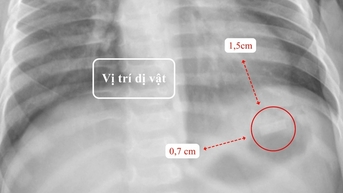

Theo các bác sĩ, hạt nở là một loại đồ chơi khá phổ biến dành cho trẻ em, có dạng những hạt nhựa nhỏ li ti, đường kính khoảng 2-5mm, với nhiều màu sắc sặc sỡ.

Khi ngâm trong nước, các hạt này có thể trương nở gấp hàng chục đến hàng trăm lần kích thước ban đầu, tạo nên hình ảnh bắt mắt, thu hút trẻ nhỏ.

Dị vật được lấy ra là những hạt nhựa nhỏ, có khả năng trương nở khi gặp nước - Ảnh: BVCC